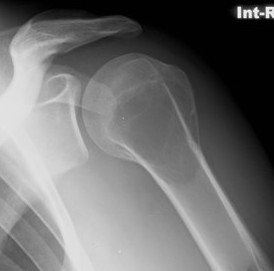

X-ray

Eccentric, sharply demarcated lytic lesion

- no sclerosis around lesion

- narrow zone of transition

- metaphysis, extending into epiphysis

- no mineralization

85% meta-epiphysis of long bones